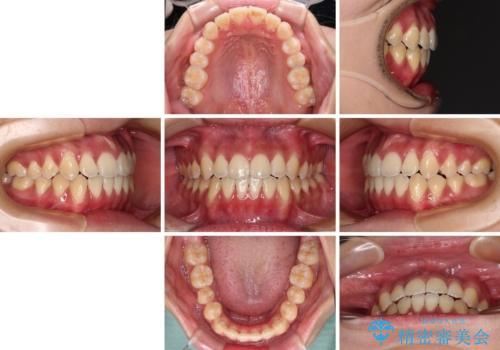

受け口と開咬を急速拡大装置とワイヤー装置で改善

- 20代女性

- メタルブラケット

- 1年3ヶ月

- 前歯の開咬と、受け口による咬み合わせの悪さを気にして来院された患者様です。

上顎歯列が狭窄していたため、急速拡大装置により上顎骨を側方に拡大し、その後ワイヤー装置にて矯正治療を行うこととしました。